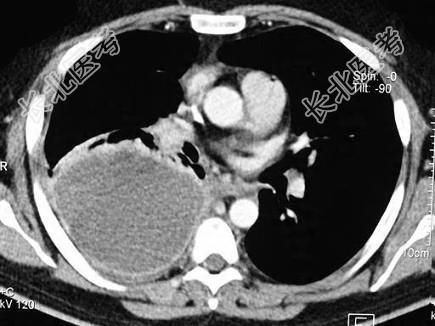

- 单项选择题男,59岁, 呼吸困难,胸痛, 有发热,请结合CT图像选择最可能的诊断 ( )

A、脓胸

B、肺脓肿

C、大叶性肺炎

D、肺囊虫病

E、肺癌